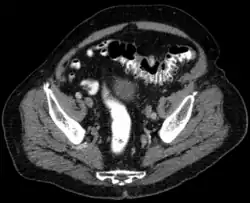

Tomografia komputerowa wykonywana jest z podaniem środka kontrastowego. Typowymi zmianami są symetryczne, zapalne zgrubienie ściany jelita grubego, rozległe nacieki tkanki tłuszczowej okołojelitowej, nagromadzenie płynu w krezce esicy i nastrzyknięcie naczyń w krezce esicy. Czułość badania ocenia się na 95%, swoistość na 35%[24]. Tomografia komputerowa ma również duże znaczenie w rozpoznaniu powikłań jak: ropnie okołojelitowe, stany zapalne otrzewnej, przetoki, i niedrożność jelit.

- Diagnostyka obrazowa uchyłkowatości i powikłań.

Obraz CT Niezmienione uchyłki esicy

Obraz CT Mały ropień w jamie brzusznej spowodowany stanem zapalnym uchyłków

Obraz CT Stan zapalny uchyłków i ropień w jamie brzusznej